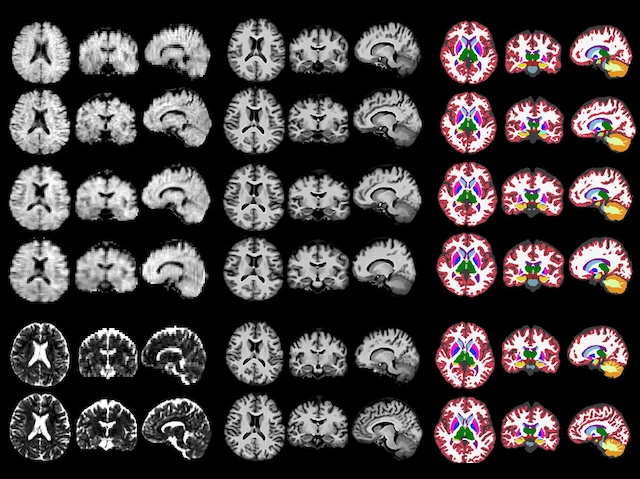

Being able to monitor brain changes in mild cognitive impairment or Alzheimer's disease at point-of-care is desirable but, because of their necessarily lower magnetic field strength, portable MRI scanners have resolution limitations due to a lower signal-to-noise ratio. Here, combination with a machine learning pipeline overcomes disadvantages and renders the portable system more freely available and cost-effective